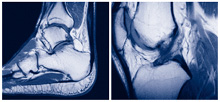

Kernspintomographie

Die Kernspintomographie eignet sich hervorragend zur differenzierten Diagnostik u. a. von Gelenkerkrankungen. Mit Hilfe von Magnetfeldern und Radiowellen werden ohne Strahlenbelastung detailreiche hochauflösende Schnittbilder Ihrer zu untersuchenden Körperregion erzeugt.